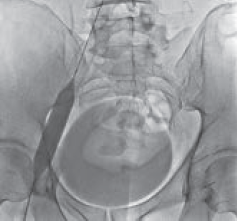

Рис. 3. Антеградная илеокаваграфия у пациента М., 39 лет, с выраженной тазовой симптоматикой (боли, эректильная дисфункция, хронический калькулезный простатит) вследствие синдрома Мея – Тюрнера: а — антеградная катетеризация левой общей подвздошной вены; б — при введении рентгеноконтрастного вещества отмечается его ретроградный заброс и контрастирование венозных сплетений малого таза (коллатеральное кровообращение); в — после контрастирования венозных сплетений малого таза рентгеноконтрастное вещество перераспределяется в правую общую подвздошную вену. Диаметр правой общей подвздошной вены в 1,4 раза меньше диаметра левой общей подвздошной вены

Рис. 4. Антеградная илеокаваграфия пациента М., 39 лет, от 28.03.2017. Отмечается компрессия левой общей и левой наружной подвздошных вен. Оперативный доступ из левой подколенной вены. Положение пациента на животе